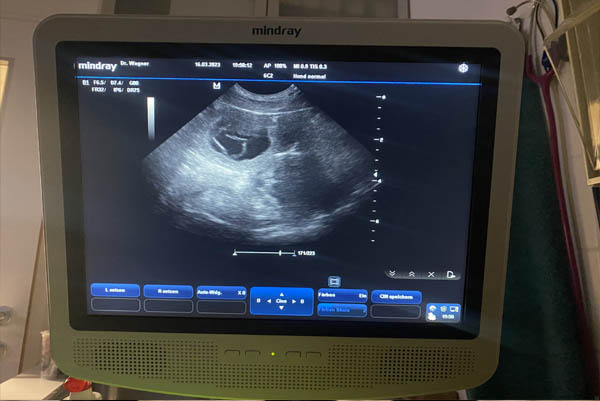

Florence is PREGNANT! The ultrasound confirmed that Florence is pregnant, and we are so excited for our puppies at the end of April.